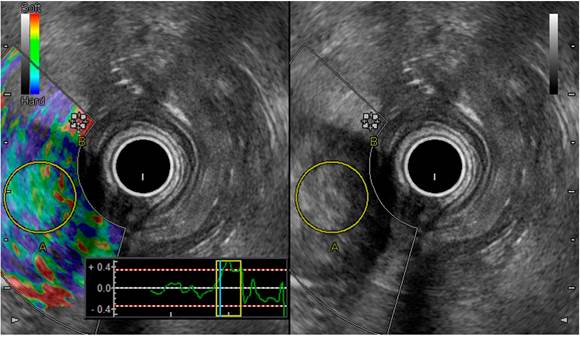

Subsequently, a qualitative blue-green elastography9 and a quantitative strain ratio of 10 and a strain histogram of 95% were performed. A 40 x 45 mm retropancreatic hyperechoic adenopathy with well-defined borders was detected in the duodenal window (Figure 4). Next, a blue elastography was documented when performing a qualitative elastography, a strain ratio of 10 and a strain histogram of 44% (Figure 5).